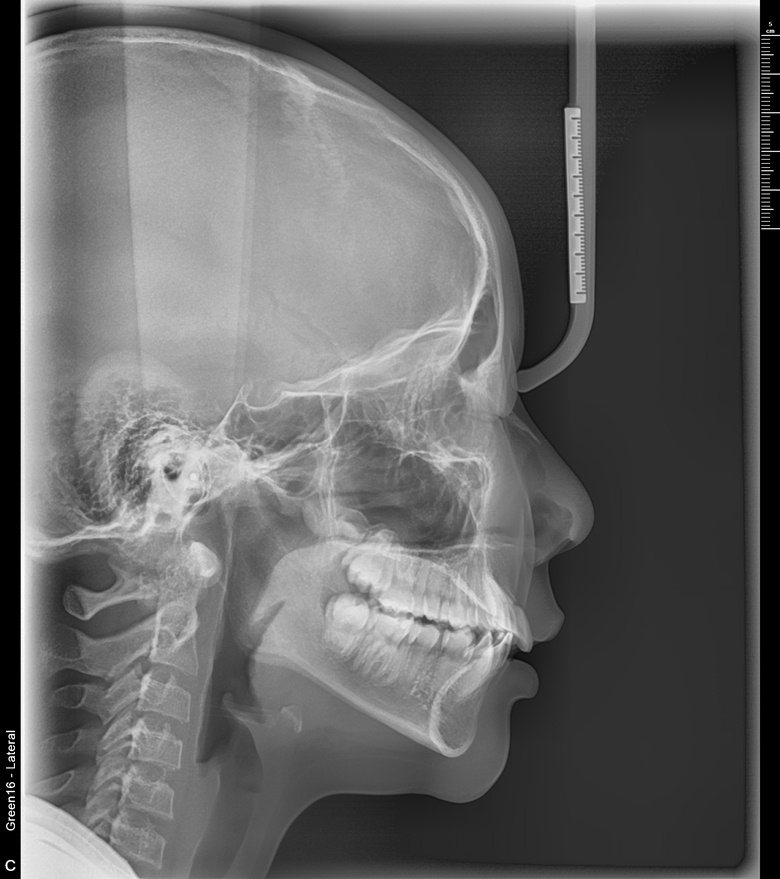

치료 전 사진입니다.